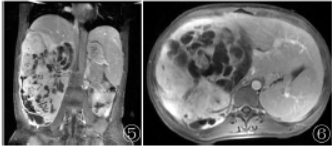

MRI检查:右侧腹膜后可见巨大团块状囊实性异常混杂信号影,呈T1WI等低、T2WI高等低信号(图3)、DWI高低混杂信号(图4),其内可见多发分隔影,增强扫描实性部分及分隔呈渐进性持续明显强化(图5,6),囊性部分未见明显强化。

图3 T2WI显示病变内信号不均匀;图4 DWI病变呈不均匀高信号;图5,6增强冠状位及轴位扫描显示病变呈不均匀强化;

在MRI由于肿瘤成分不同,信号表现为多样化,在T1WI主要呈低或等信号,少数可见稍高出血信号,T2WI主要呈高信号或混杂信号,部分瘤内可见T2WI高信号分隔,DWI呈高信号,增强扫描肿瘤实性部分呈不均匀延迟强化,另外,少数肿瘤周围可见包膜,T2WI序列呈环形低信号。UPS较特征性的表现是坏死囊变及特征性的“假包膜征”、“纤维分隔征”、“尾征”。

本例为青年女性,临床表现为腹胀,影像检查提示腹膜后巨大团块状不均匀软组织密度/信号影,增强扫描呈不均匀强化,可见坏死囊变,与上述影像表现基本一致。